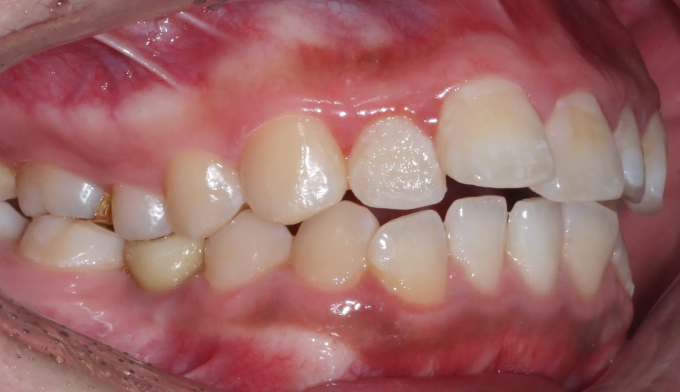

돌출입과 불규칙한 앞니를 가지고 있습니다. 그리고 아래쪽에 ‘임플란트’가 있습니다.

임플란트는 뼈와 강력히 결합되어 있기 때문에 교정치료로 절대 움직일 수 없습니다. 따라서 해당 부위는 절대 교정치료로 움직일 수 없다는 제한점이 있는 상태에서 교정치료를 진행하게 되었습니다.

돌출입을 해소하고 앞니를 가지런하게 만들기 위한 공간을 만드는 과정중에는 저 임플란트를 꼭 제거해야 했으나, 최대한 발치 없이 교정을 진행하였습니다.

후방이동이 불가하므로 악궁확장을 통하여 공간확보를 시도하였고, 동시에 돌출감도 해소되었습니다.